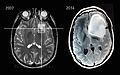

Astrocytoma.jpg

Two PET images — the upper of which shows a normal brain and the lower shows astrocytoma.